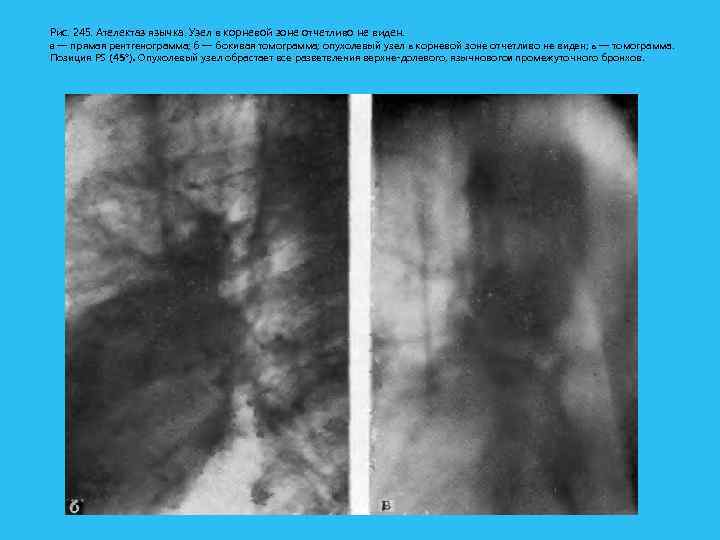

Рис. 245. Ателектаз язычка. Узел в корневой зоне отчетливо не виден. а — прямая рентгенограмма; б — бокивая томограмма; опухолевый узел в корневой зоне отчетливо не виден; в — томограмма. Позиция PS (45°). Опухолевый узел обрастает все разветвления верхне долевого, язычновогои промежуточного бронхов.